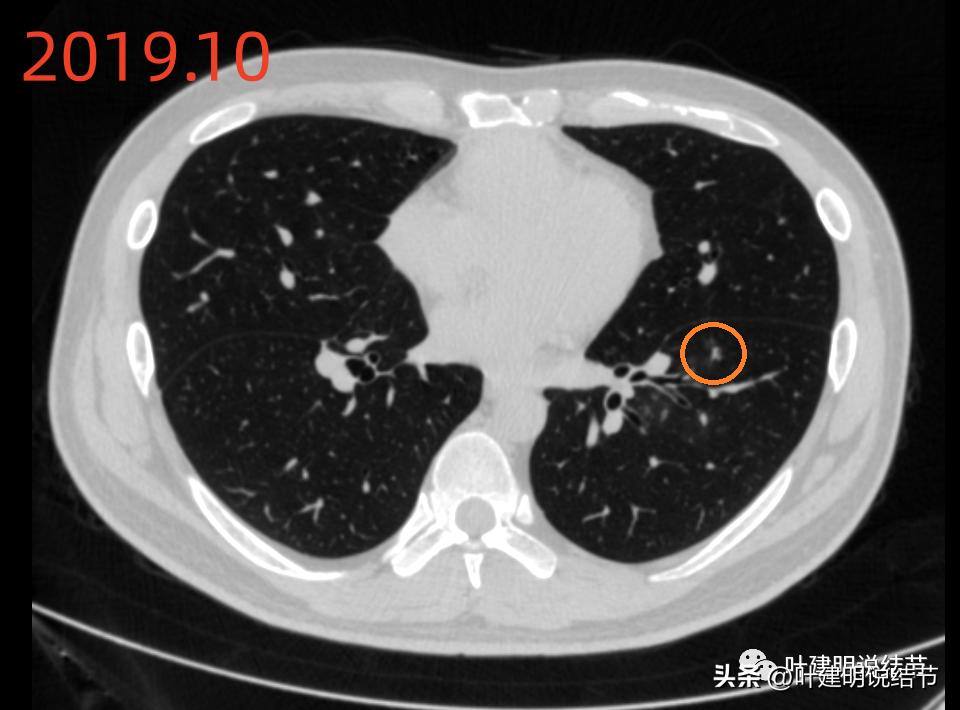

再看2019年时的影像:

当时病灶A就有,密度比现在感觉还略高,膨胀性更不足点。至少到2022年,病灶说不上明显进展。

当时左上有微小高密度结节(以下称病灶C),考虑良性可能性大。

右中叶有淡磨玻璃结节(以下称病灶D),考虑慢性炎伴纤维增生或肺泡上皮增生可能性大。

当时左下有肺炎。

先看2022年6月的片子时,感觉左下叶红色圈起来的像原位癌,桔色圈起来的像不典型增生可能性大些。但回顾2019年的片子,当时有肺炎,如绿色圈起来的范围内都是炎症性的,那时候这两个病灶也有,但红色这处当时瘤肺边界模糊点,桔色这处密度比现在感觉要高点,又结合当时炎症过,所以总体看来,桔色的考虑慢性炎性结节可能性大;红色的虽不能除外原位癌,但也无法除外炎性,至少风险应该不算高,如果再随访下也可以的。若手术,红色的要后基底段切除,桔色的要前内基底段切除,就留下外基底段与背段感觉有些孤立;若均楔形切除也是可以的,但若均是炎性,则不划算,我个人意思仍是风险不大情况下,再观察下,反正危险不大嘛!